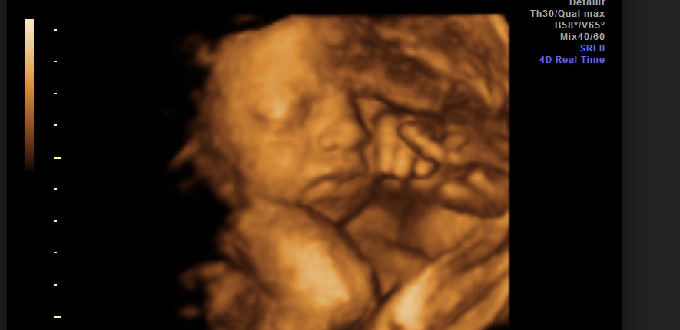

(LifeNews/InfoCatólica) El número de abortos que tuvieron lugar en Inglaterra y Gales durante 2020 es el «más alto desde que comenzaron los registros», según el Departamento de Salud y Asistencia Social. Las cifras, que se dieron a conocer, revelan que 210.860 niños no nacidos fueron asesinados por abortos durante 2020. Este es el número más alto de abortos desde que se introdujo la Ley de Aborto de 1967.